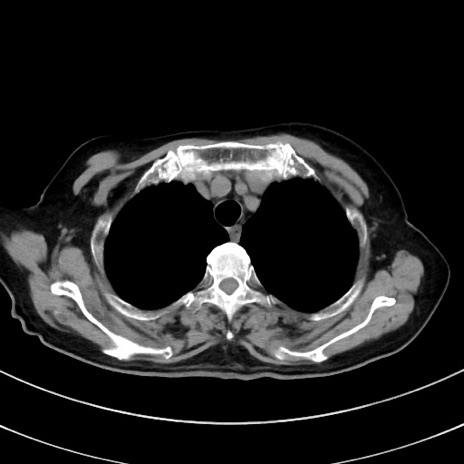

症例33(横断像)

【症例】70歳代 女性

【主訴】心窩部痛

【現病歴】延髄病変の精査・加療にて神経内科入院中。本日より心窩部痛あり。

【既往歴】虫垂炎

【身体所見】右下腹部を中心に圧痛と反跳痛あり。

【データ】WBC 10900、CRP 0.02